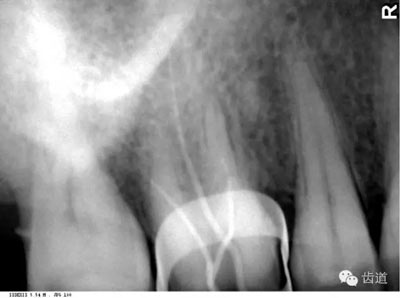

4)外斜線:

由升支前緣下部斜向前下方,為一密度高的帶狀影像。常重疊在第二、三磨牙牙冠處、頸部或根部,使牙髓室或根管不能清晰顯示

9)內(nèi)斜線:

為自頦嵴斜向上后的致密線條影,至升支前緣消失,位于外斜線之下,走行方向與其一致。